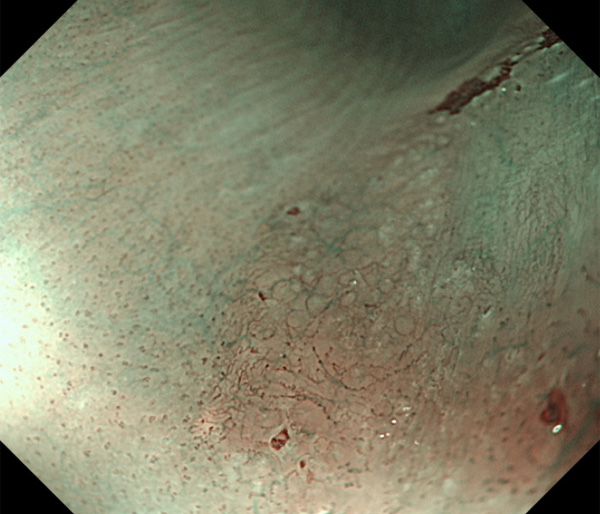

内視鏡所見と病理組織像の1対1対応が可能な症例を公募いたします。主にLSBEに発生した早期癌(HGDを含む)を対象としますが、興味深い症例であればSSBE癌でも結構です。採否は世話人へご一任ください。

症例呈示希望者は応募用紙に記入の上、代表的な内視鏡(2枚)、切除標本(新鮮、固定)、切り出し図、マッピング、代表的組織像とともに、Barrett 食道研究会事務局 barrett.shinshu@gmail.comへお申し込み下さい(10MB以下でお願い致します)。

特に、本邦では極めて稀なlong segment Barrett’s esophagus(LSBE)から発生した早期癌は、診断に難渋する場合も多く、欧米ではランダム生検による検出が標準的とされています。背景のBarrett食道もろとも全体を内視鏡切除+ラジオ波焼灼する欧米と異なり、ESDで内視鏡的な局所切除が基本の本邦では、存在診断+範囲診断(特に水平)を的確に行うことが不可欠です。

そのためには、一流の病理医による組織学的診断とエキスパート内視鏡医による拡大内視鏡像との一対一対応を徹底的に行うことで、『本来、見えないであろう拡大所見の先にある組織構築像が診えてくる』所まで内視鏡診断レベルを上げていく必要があります。その実現には、一対一対応を追究した症例(特にLSBE発生例)1例でも多く経験するしかありません。本研究会でBarrett食道腺癌(LSBE発生早期病変)を共に学び、拡大内視鏡像の一歩先を診るスキルを習得しましょう!一人でも多くの皆様のご参加をお待ちしています。

私は、Barrett食道癌はHGDも含め、内視鏡による存在診断、範囲診断が可能と信じて来ました。しかし最近、NBI拡大観察を併用しても側方範囲診断が不可能なLSBE症例を経験しました。診断技術を向上させるためには、多くの症例を診るしかありません。そこで、Barrett食道に造詣の深い先生方に世話人をお願いし、Barrett食道研究会を立ち上げることに致しました。全国からLSBE症例を集め、内視鏡的、組織学的診断に迫りたいと思います。皆様のご参加をお待ち致します。